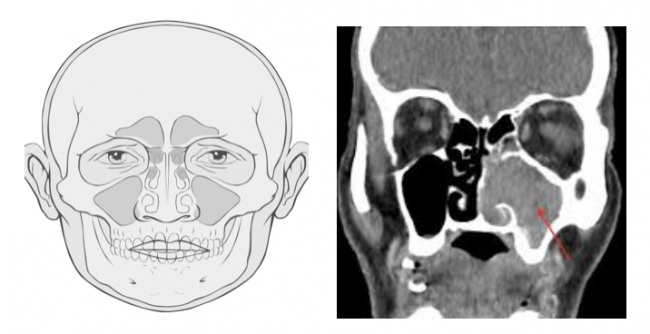

Структуры пазух носа, также называемые придаточными пазухами носа, представляют собой 4 пары воздушных пространств, расположенных внутри лицевых костей, и каждая названа в честь костных структур, в которых они расположены (верхнечелюстная, решётчатая, лобная и клиновидная пазухи). Пазухи, которые частично присутствуют при рождении, почти полностью развиваются примерно к 12-14 годам. Он имеет такие функции, как увлажнение вдыхаемого…